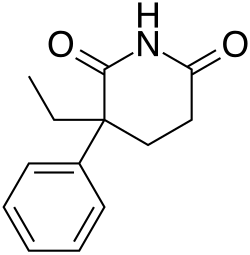

Piperidinediones

Piperidinediones are a class of depressants that are not used anymore. There are piperidinediones that are used for other purposes, like breast cancer.[158][159][160] The piperidinedione class is very structurally similar to barbiturates. Some piperidinediones include glutethimide, methyprylon, pyrithyldione, glutarimide, and aminoglutethimide. The first three (glutethimide, methyprylon, and pyrithyldione) are central nervous depressants. The piperidinedione depressants, specifically glutethimide, are positive modulators of the GABAA anion channel. The drug increases inhibitory GABAergic tone and causes neuro-inhibition of the cortical and limbic systems, observed clinically as a sedative-hypnotic effect.[161] Glutethimide is also a potent inducer of the CYP 2D6 enzyme in the liver. This enzyme is responsible for converting many drugs, from beta blockers to antidepressants to opioids and opiates. Due to its effects on the conversion of opioids, it was highly abused and mixed with opioids like codeine. Codeine must be metabolized to morphine in the liver to have its psychoactive and analgesic effects. Mixing codeine with glutethimide allowed more codeine to be converted into morphine in the body, thus increasing its effect. These were known as "hits", "cibas and codeine", and "dors and 4s". Glutethimide was believed to be safer than barbiturates, but many people died from the drug. Demand was high in the United States at one point. Production of glutethimide was discontinued in the US in 1993 and in several eastern European countries, most notably Hungary, in 2006.